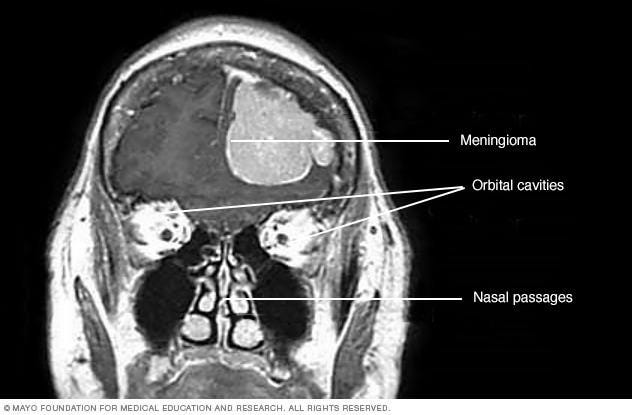

Depo-Provera (Brain Tumor Claims)

Depo-Provera is an injectable contraceptive. Lawsuits allege that prolonged use of the drug is associated with the development of meningiomas, a type of brain tumor that can cause serious neurological symptoms. Plaintiffs claim that the risks were not adequately disclosed. This litigation has expanded quickly and is now centralized in federal court. With thousands of claims already filed, the case is moving at a faster pace than many traditional pharmaceutical mass torts, and early trial settings are anticipated, making it one of the most closely watched emerging dockets.